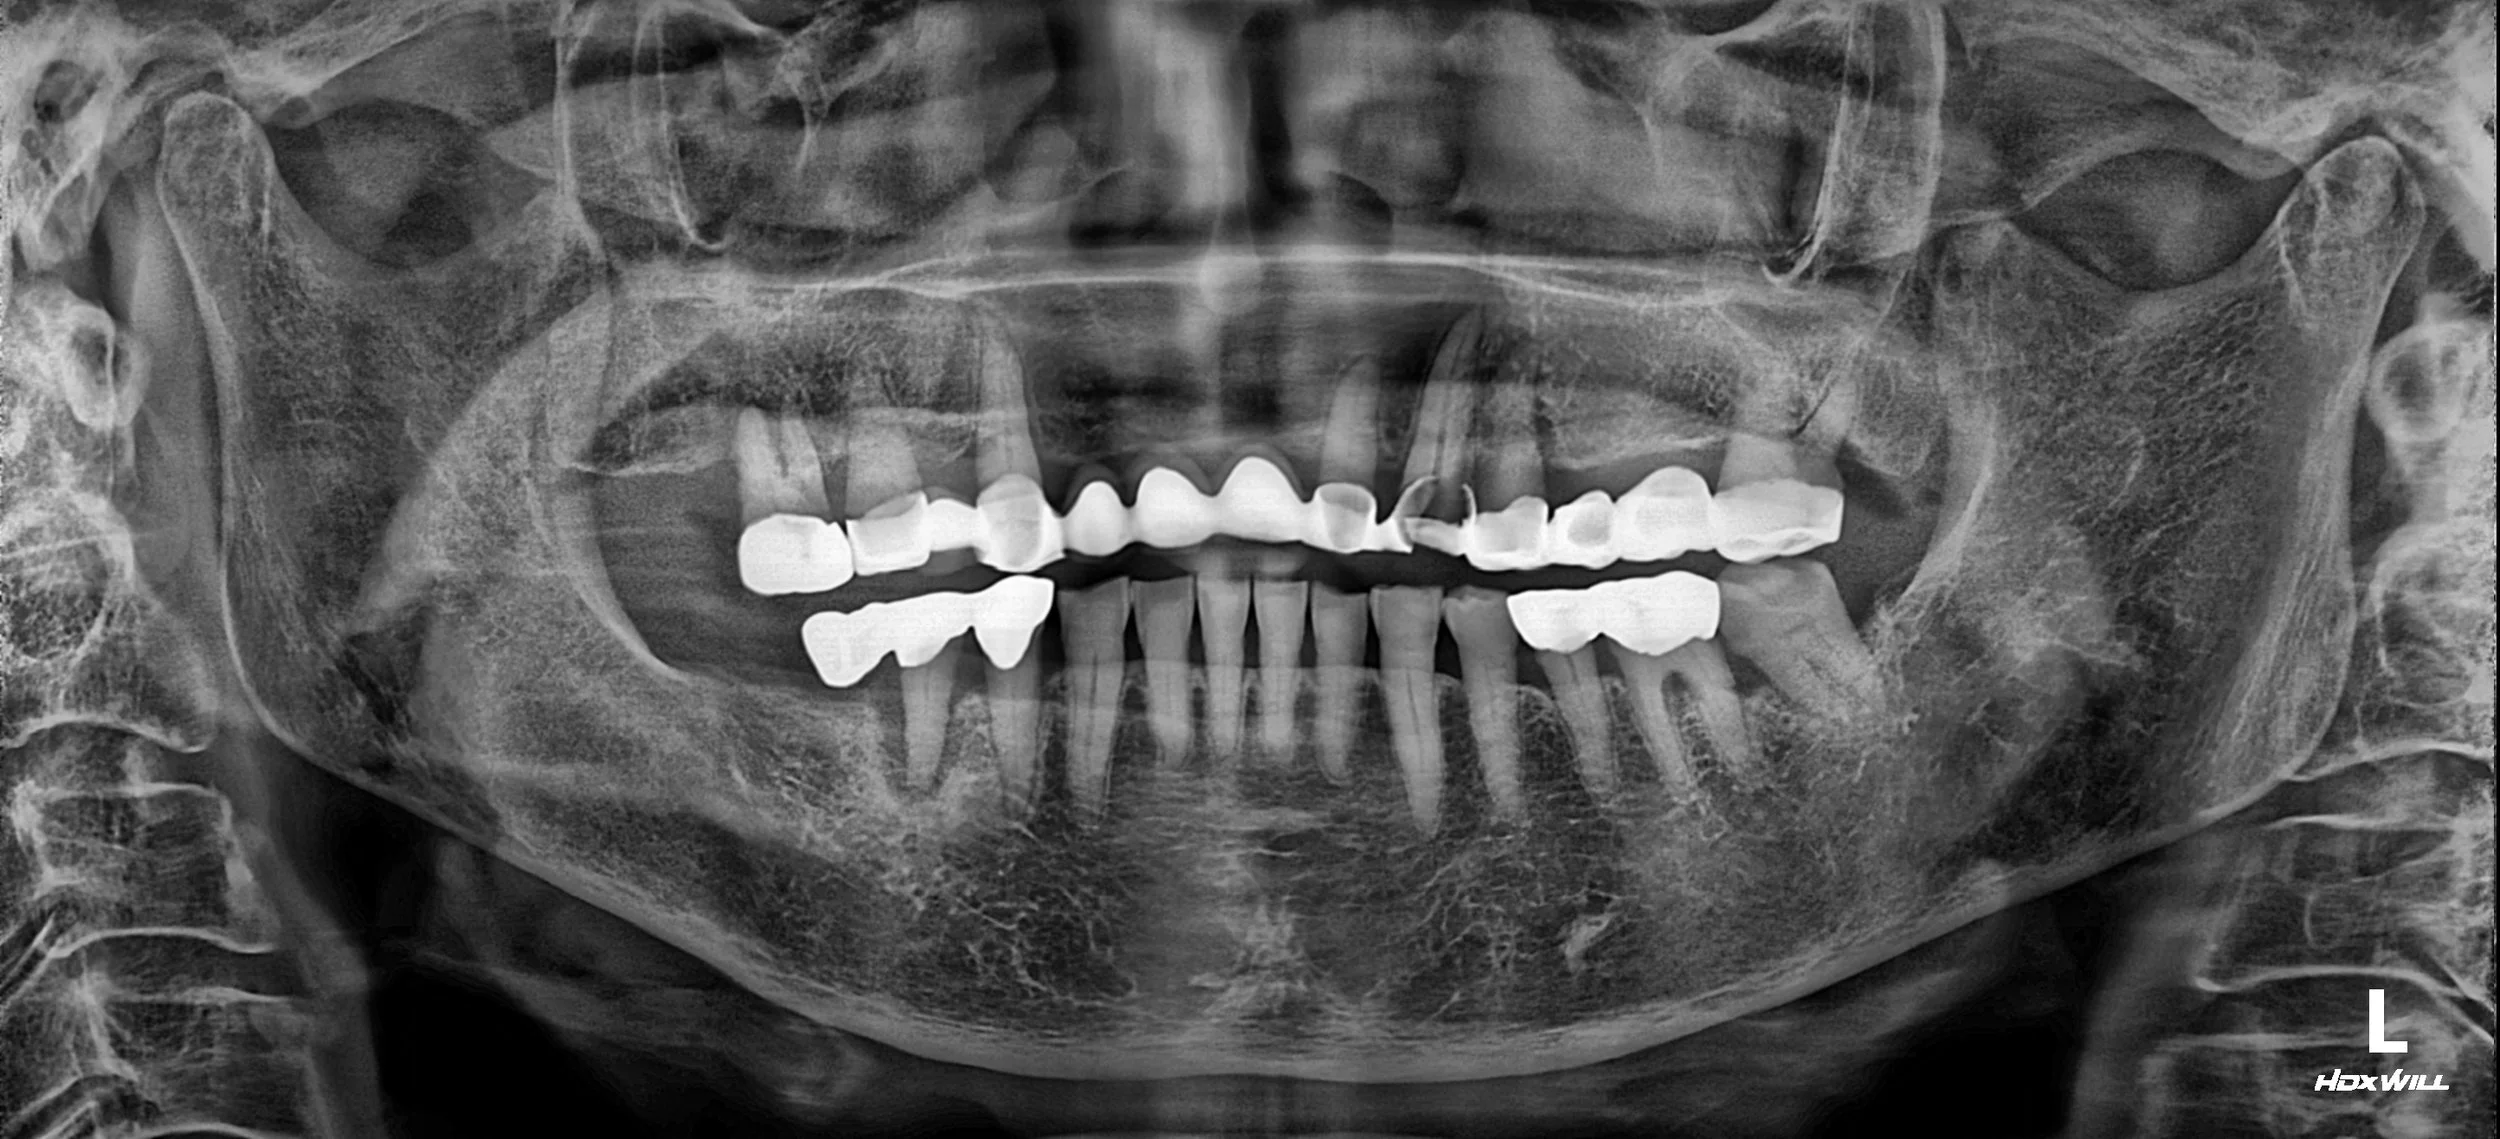

OPG - AFTER